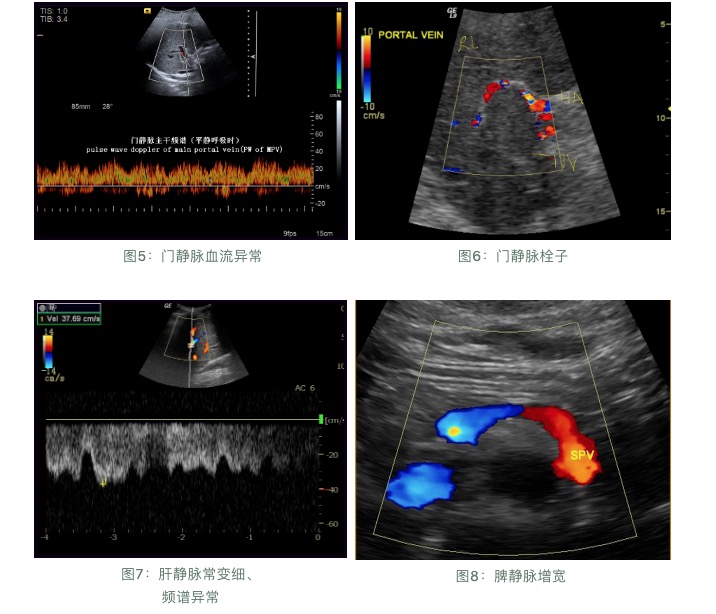

超聲檢查:

肝臟受病毒感染和發(fā)生炎癥后,就會造成肝臟內(nèi)部的結(jié)構(gòu)損傷,從局部的纖維化、結(jié)節(jié)性肝硬化到最后的全面硬化,超聲檢查是早期發(fā)現(xiàn)肝硬化的最直接指標(biāo)。